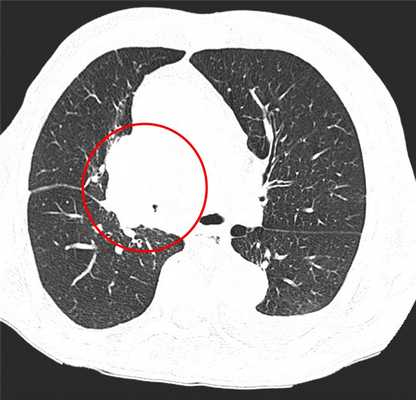

Фото 1 — Центральный рак правого нижнедолевого бронха (1) с обтурацией и метастазами (2) в бифуркационные лимфатические узлы

КТ-признаки центрального рака легкого: при компьютерной томографии определяется объемное образование мягкотканной структуры, в котором «обрывается» просвет нижнедолевого бронха. Края образования бугристые, неровные, со спикулами, форма неправильная.

Центральный рак легкого на КТ. Обратите внимание на различия в ширине просвета центральных бронхов справа и слева. Просвет правого верхнедолевого бронха не виден. Виден ателектаз верхней доли. В круге - непосредственно само опухолевое образование, ставшее причиной ателектаза.